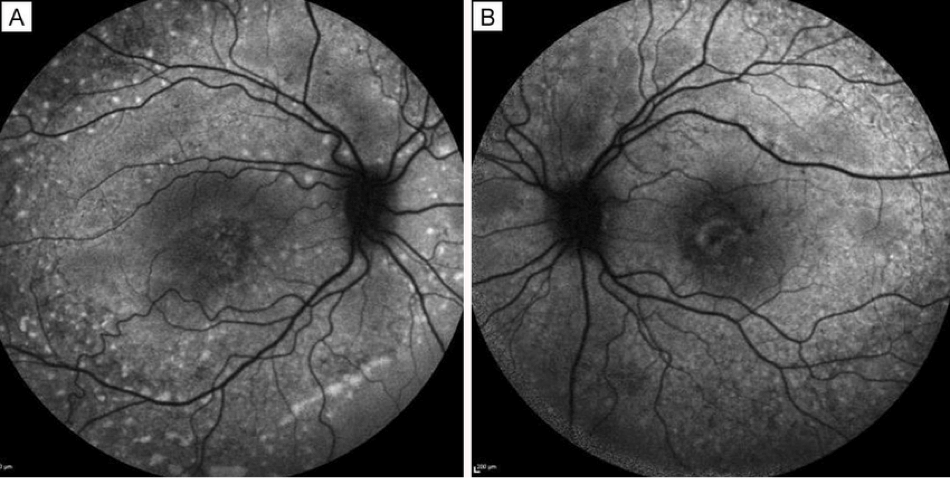

Autofluorescencia del fondo de ojo

La autofluorescencia del fondo de ojo es una importante técnica de imagen para el diagnóstico y monitorización de la DMAE, en particular de la DMAE avanzada seca o atrofia geográfica (AG).11 Se utiliza una luz específica (normalmente azul) para producir la autofluorescencia de una molécula llamada lipofuscina, que suele estar distribuida uniformemente por toda la retina.8 Las regiones no sanas de la retina pueden aparecer más oscuras en el caso de las zonas atróficas, o más brillantes en el caso de las drusas, ambos signos de DMAE.8,13 Elpatrón de fluorescencia puede indicar la potencial tasa de progresión de la DMAE de un paciente.14